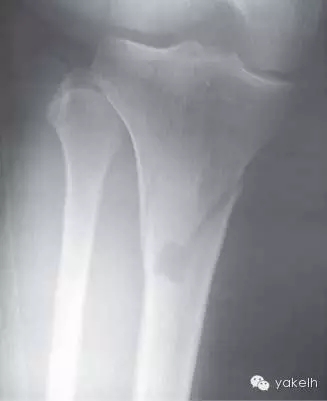

¤¤中等麻藥鎮(zhèn)痛劑可很好緩解脛骨取骨的術(shù)后疼痛。供區(qū)遠(yuǎn)端腿部的瘀斑很常見。該區(qū)域的取骨手術(shù)很少發(fā)生并發(fā)癥,可能會(huì)發(fā)生的并發(fā)癥有血腫形成、傷口裂開、感染、骨折。盡管很少,大部分脛骨骨折是由于腿部取骨位置過低而引起的(圖13.14)。

圖13.14 由于腿部取骨位點(diǎn)過低,導(dǎo)致少見的脛骨骨折。